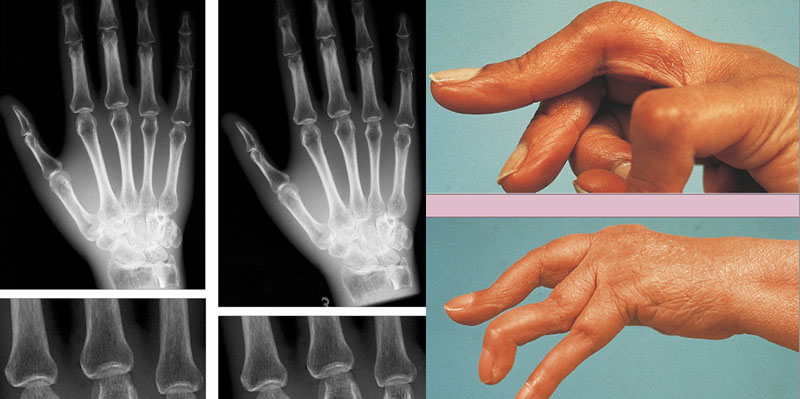

Τα συμπτώματα του συνδρόμου Felty είναι παρόμοια με αυτά της ρευματοειδούς αρθρίτιδας.

Οι ασθενείς πάσχουν από επώδυνες, δύσκαμπτες και πρησμένες αρθρώσεις, συνήθως, στις αρθρώσεις των χεριών και των ποδιών.

Ρευματοειδής αρθρίτιδα

Η ρευματοειδής αρθρίτιδα είναι μια αυτοάνοση ασθένεια που χαρακτηρίζεται από φλεγμονή των αρθρώσεων λόγω προσβολής από το ανοσοποιητικό σύστημα του ίδιου του σώματος. Σε αυτήν την κατάσταση, τα λευκά αιμοσφαίρια ταξιδεύουν μέσω της ροής του αίματος στις αρθρώσεις και απελευθερώνουν προφλεγμονώδεις κυτοκίνες. Το αποτέλεσμα αυτής της χημικής απελευθέρωσης κάνει τα αρθρικά κύτταρα να απελευθερώνουν επιβλαβείς χημικές ουσίες σε απόκριση, καθώς και να ξεκινήσουν την ανάπτυξη νέων αιμοφόρων αγγείων. Τα νεοσχηματισμένα αγγεία μεγαλώνουν προς τα μέσα, εισβάλλοντας στον αρθρικό χόνδρο και στα οστά εντός της άρθρωσης. Η βλάβη στον κάποτε υγιή ιστό προκαλεί φλεγμονή και τελικά συσσώρευση υγρού στην άρθρωση και οι αρθρώσεις διογκώνονται, μειώνοντας αργά το χώρο που κρατά τα οστά να μην έρχονται σε επαφή μεταξύ τους. Εάν δεν αντιμετωπιστεί αυτή η κατάσταση, ο χώρος των αρθρώσεων μικραίνει, εντελώς, προκαλώντας αγκύλωση. Στο προχωρημένο στάδιο της αγκύλωσης, η κινητικότητα των αρθρώσεων επηρεάζεται, πολύ. Η πρώιμη παρουσίαση παρατηρείται, συνήθως, στις αρθρώσεις των χεριών και των ποδιών. Καθώς, η ασθένεια εξελίσσεται, μπορεί να παρουσιαστεί στα γόνατα, τους καρπούς, τους γοφούς και τους ώμους. Αυτή η κατάσταση μπορεί να επηρεάσει και να βλάψει πολλά άλλα συστήματα του σώματος, όπως τα μάτια, την καρδιά, τους πνεύμονες και τα αιμοφόρα αγγεία. Η ρευματοειδής αρθρίτιδα είναι μια κατάσταση που δεν μπορεί να θεραπευτεί, αλλά τα συμπτώματα μπορούν να αντιμετωπιστούν χρησιμοποιώντας συγκεκριμένα φάρμακα μόνα τους ή σε συνδυασμό. Λόγω της αυξημένης φλεγμονώδους απόκρισης του ανοσοποιητικού συστήματος του σώματος, αυτή η κατάσταση μπορεί να προκαλέσει μείωση των ερυθρών και λευκών αιμοσφαιρίων.